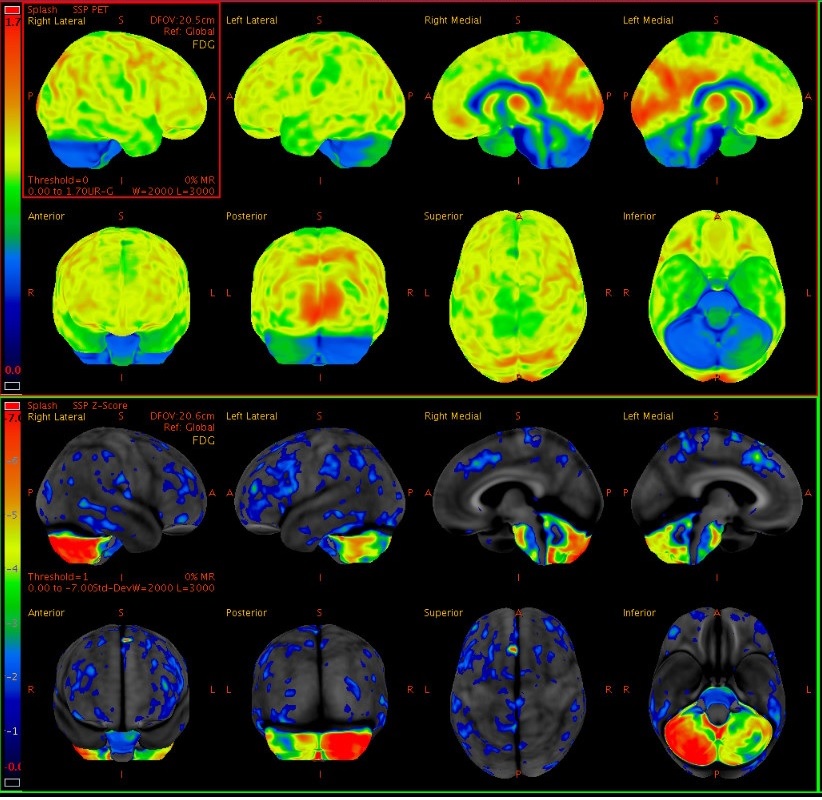

Results: The patient developed progressive issues with speech production beginning at age 28 which advanced over months. The following year she developed gait issues which resulted in falls within a year of onset, and difficulty coordinating her right upper extremity. Neurologic examination at time of initial evaluation at our center, 19 months after symptom onset, was notable for a wide-based ataxic appearing gait, and she was unable to tandem walk due to unsteadiness. There was mild upper extremity ataxia and dysmetria, mild to moderate ataxia with heel-to-shin movements, and subtle parkinsonian features. Speech pathology evaluation revealed a slow speaking rate with inter word segmentation, revisions and restarts, apractic sound errors and a reduced range of prosodic variation, with slow but otherwise normal speech AMRs. MRI of the brain 19 months after symptom onset showed cerebellar atrophy with prominent involvement of the right greater than left cerebellar hemisphere [figure1] and corresponding hypometabolism was seen on FDG brain PET CT [figure2]. AP3B2 antibody was positive in serum and CSF on tissue immunofluorescence and cell binding assay. FDG body PET CT showed no evidence of malignancy. She noted improvements in mobility and balance four weeks after starting methylprednisolone and mycophenolate.

Figure 2